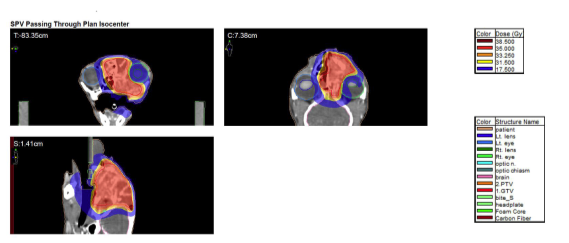

03 치료 계획

· 목표: 통증 완화 및 삶의 질 개선

· 방법: 적은 횟수의 고선량 방사선치료

· 부작용: 종양이 침습한 쪽 눈의 불편감은 감수

치료 중 일시적인 통증 악화로 중단을 고민하기도 했지만, 마약성 진통제 병행으로 무사히 치료를 마쳤습니다.

고양이 구강 SCC 방사선 치료용 모의 CT 촬영 / 출처: 에스동물암센터